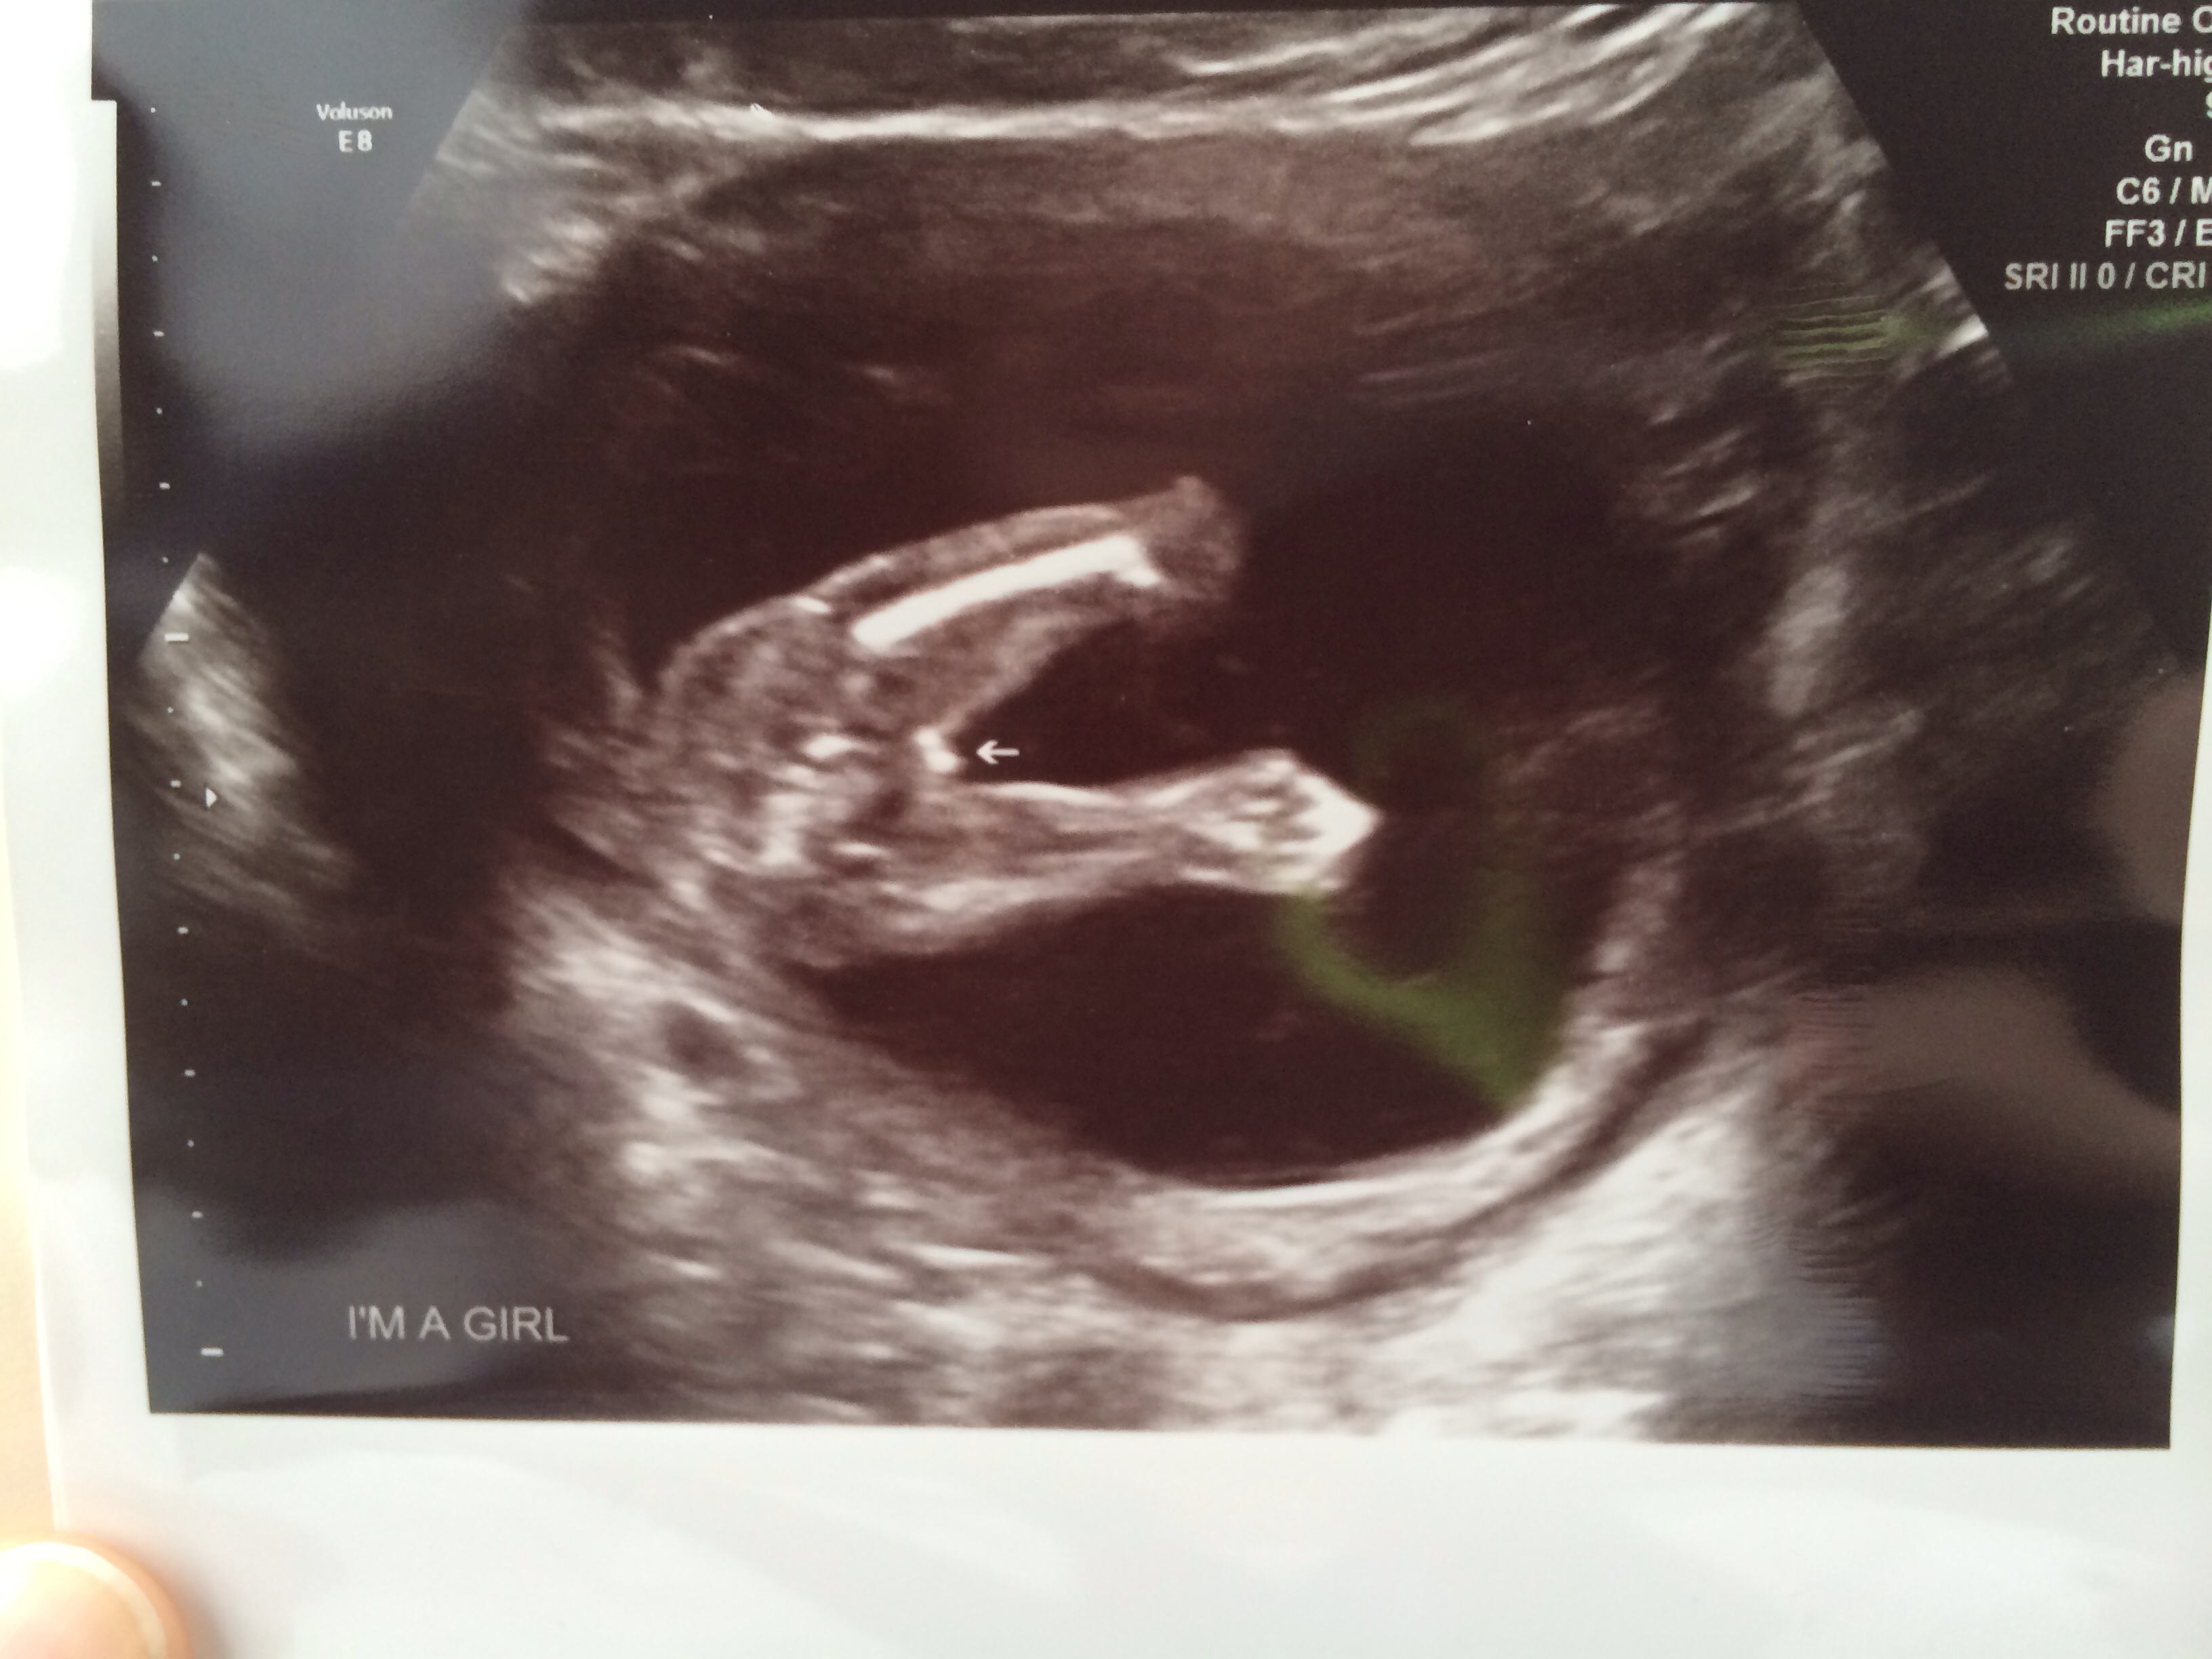

Attachment 15884Attachment 15883Please look closely. Determined GIRL after a very quick 16 week ultrasound, but not so sure!

Second picture is definitely a girl. Congrats! x

The black spot on photo 2 is very misdirecting. Make sure you zoom in and look through it. Also notice the faint grey line next to the leg. We have our anatomy scan in just under three weeks. Going to be happy with a healthy baby! But curious! :))

Girl, girl, girl. I zoomed those suckers in and am seeing nothing but female parts. Congrats :)